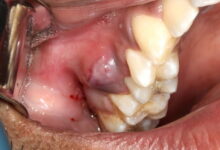

سفیکسیم یک داروی آنتی بیوتیک است که برای درمان عفونتهای دندان استفاده میشود. این دارو از خانواده پنیسیلینها است و میتواند در موارد مختلفی از جمله عفونتهای باکتریایی دندان، عفونتهای لثه و عفونتهای جراحی دندان استفاده شود. این مطلب جنبه آموزشی و اطلاع رسانی دارد، در صورت مشکل به دندانپزشک مراجعه کنید.

استفاده از سفیکسیم در درمان عفونتهای دندان مزایایی دارد. اولاً، این دارو بسیار موثر در کاهش علائم عفونتهای دندان است. علائمی مانند درد، تورم و قرمزی را میتوان با استفاده منظم از سفیکسیم کاهش داد. همچنین، سفیکسیم میتواند در پیشگیری از عفونتهای جدید نیز موثر باشد.